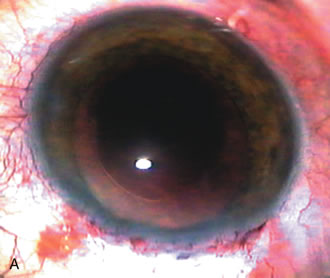

CATARACT EXTRACTION ALONE REDUCES IOP IN MOST EYES WITH ANGLE-CLOSURE GLAUCOMA

Uncomplicated cataract extraction substantially reduces IOP, along with the number of postoperative glaucoma medications in eyes with angle-closure glaucoma.146,147 When preoperative gonioscopy reveals PAS, along with adjacent areas of appositional closure, lens extraction alone in select cases may be a reasonable alternative to filtration surgery.148,149 Phacomorphic angle-closure disease due to enlargement of the lens with progressive angle crowding is eliminated following lens extraction. The width and depth of the anterior chamber angle in eyes with angle-closure glaucoma increases significantly after cataract extraction with IOL implantation and becomes similar to open-angle glaucoma and normal eyes.150,151 (Fig. 5). Combining phacoemulsification, IOL implantation, and limited goniosynechialysis is effective in the treatment of cataract and chronic angle-closure glaucoma.152 Phacoemulsification with implantation of a foldable IOL is more effective in reducing IOP and improving visual acuity than surgical peripheral iridectomy in eyes with acute angle-closure glaucoma.153

Fig. 5. Anterior chamber angle changes associated with lens extraction and PCIOL This 65-year-old Vietnamese woman has a long-standing history of chronic angle-closure glaucoma treated with laser peripheral iridectomy. The optic nerve demonstrated mild glaucomatous damage and IOP was moderately controlled on two antiglaucoma medications. The cataract was removed through temporal clear corneal phacoemulsification with foldable acrylic IOL. A. Symptomatic cataract in narrow-angle glaucoma eye with patent iridectomy. B. Intraoperative goniophotograph showing crowding of angle with increasing narrowness due to phacomorphic component. C. Intraoperative photograph showing temporal clear corneal approach with IOL in the capsular bag. D. Intraoperative goniophotograph demonstrating deepening of chamber angle following lens extraction. Proposed theories for IOP reduction following lens extraction with complete wound closure:

1. Anterior chamber deepening with improved access to trabecular meshwork

2. Increase in traction on the trabecular meshwork

3. Improved outflow facility mediated by an increase in prostaglandin release

4. Reduction in aqueous humor production

5. Atrophy of ciliary body processes

6. Goniosynechialysis due to intraoperative over deepening of AC with viscoelastic

7. Relief of undiagnosed pupil block